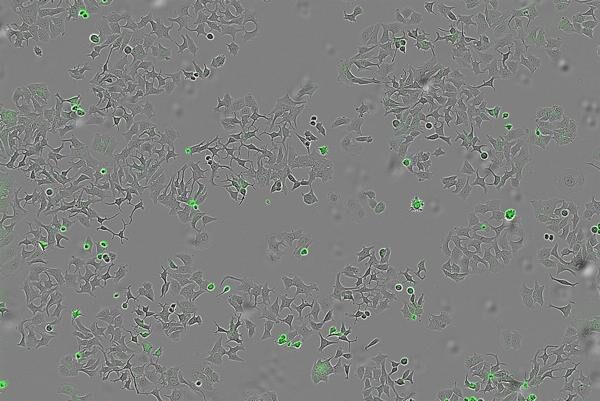

Para desarrollar este estudio se cultivó la bacteria ‘vibrio cholerae’, contando con una cepa normal y otra mutante modificada genéticamente, y posteriormente se recogió ‘supernatante’, que es el líquido donde crecen estas bacterias y que también contiene las proteínas y sustancias liberadas por la bacteria, y se aplicó a células cancerosas humanas de colon, mama y páncreas para observar qué efectos producía.

«Lo que buscamos fue comprobar si las células humanas de distintos tipos tumorales (mama, colon y páncreas) seguían vivas y si podían multiplicarse tras estar en contacto con estas sustancias bacterianas, en particular con la proteína HapA«, ha explicado explica Hurtado.

En la investigación han empleado sistemas avanzados de imagen en tiempo real que permiten contar células vivas y muertas, y medir la apoptosis (muerte programada) para observar con precisión el bloqueo de las vías.